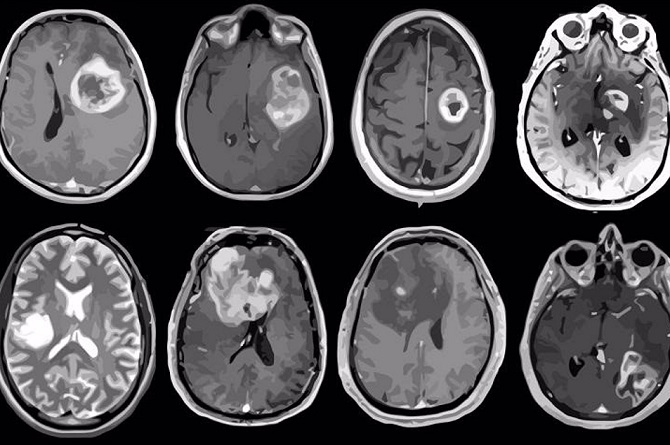

Una terapia combinada podría mejorar la supervivencia de los pacientes con tumores cerebrales

El equipo liderado por Massimo Squatrito, jefe del Grupo de Tumores Cerebrales Fundación Seve-Ballesteros del Centro Nacional de Investigaciones Oncológicas (CNIO), propone una novedosa estrategia terapéutica basada en la combinación de temozolomida y dianhidrogalactitol, fármaco en fase de ensayos clínicos y ya aprobado para el tratamiento de tumores, que podría mejorar la supervivencia de los pacientes con tumores cerebrales agresivos.

Los glioblastomas son los tumores cerebrales más frecuentes y más agresivos, con una tasa de supervivencia que apenas ha aumentado en los últimos 50 años, lo que pone de manifiesto la necesidad urgente de desarrollar nuevas estrategias terapéuticas. En la actualidad, el principal y casi único tratamiento para los glioblastomas es la combinación de radioterapia con el agente de quimioterapia llamado temozolomida, previa resección quirúrgica de la masa tumoral.